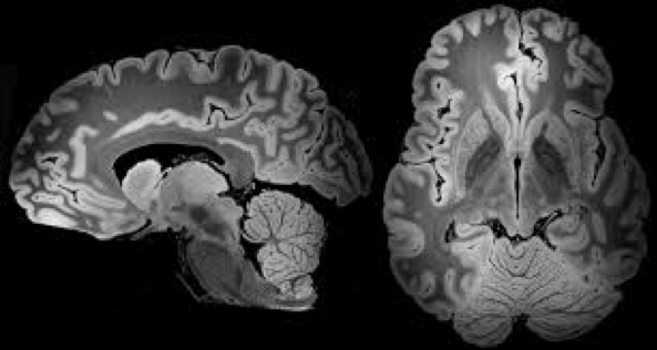

گروههایی با تخصص فیزیک و شیمی در حال توسعه سخت افزار و نرم افزار تکنولوژیکی برای روشهایی مانند الکتروانسفالوگرافی (EEG)، تصویربرداری رزونانس مغناطیسی عملکردی (fMRI) و توموگرافی گسیل پوزیترون (PET) هستند. دیگران با تخصص در مدل سازی محاسباتی در حال توسعه روشهای تجزیه و تحلیل برای مجموعه دادههای بزرگ و پیچیده هستند که توسط روشهای تصویربرداری عصبی تولید میشوند. در نهایت، بیوفیزیکدانان این روشها را برای مطالعه سیستمهای عصبی در پردازش حسی و شناختی در حیوانات و انسانها و در سلامتی و بیماریها به کار میبرند.

روشهای پزشکی از طریق بیوفیزیک به میزان قابل توجهی بهتر شده اند. با استفاده از اشعههای نوری و مغناطیس، تکنیکهای CAT و MRI و PET توسعه یافت که تصویربرداری سه بعدی و دسترسی به نمای داخلی بدن انسان کمک میکند. تصور این درمانها بدون چنین امکانات مدرن غیرممکن است. همچنین، ضربان سازها و کاردیوگرافها از الکتریسیته برای درک انقباض ماهیچهها و تکانههای عصبی استفاده میکنند. به عنوان مثال در MRI، از آهن ربا برای تراز کردن پروتونهای بدن با میدان مغناطیسی استفاده میشود. سپس یک جریان فرکانس رادیویی عبور میکند و پروتونها را از حالت تعادل میچرخاند. پس از حذف جریان، زمان لازم برای تنظیم مجدد پروتونها با میدان مغناطیسی و همچنین انرژی آزاد شده اندازه گیری میشود. بر این اساس، بافتها متمایز میشوند و تصویر دقیقی از بدن انسان به تصویر کشیده میشود.